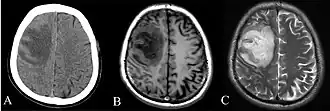

Depending on the course of infection, other severe manifestations develop. Approximately 1 to 5% of those infected develop inflammation of the brain and brain covering or brain abscess; 14 to 28% develop pyelonephritis, kidney abscess or prostatic abscesses; 0 to 30% develop neck or salivary gland abscesses; 10 to 33% develop liver, spleen, or paraintestinal abscesses; and 4 to 14% develop septic arthritis and osteomyelitis.[1] Rare manifestations include lymph node disease resembling tuberculosis,[10] mediastinal masses, pericardial effusion,[3] mycotic aneurysm,[1] and inflammation of the pancreas.[3] In Australia, up to 20% of infected males develop prostatic abscess which may manifest clinically as pain during urination, difficulty in passing urine, and urinary retention requiring catheterisation.[1] Rectal examination may find enlarged prostate.[3] In Thailand, 30% of the infected children develop parotid abscesses.[1] Encephalomyelitis not only happens in those with risk factors but can also occur in healthy people without risk factors. Those with melioidosis encephalomyelitis tend to have normal computed tomography (CT) scans but increased T2 signal by magnetic resonance imaging (MRI), extending to the brain stem and spinal cord. Clinical signs include: unilateral upper motor neuron limb weakness, cerebellar signs, and cranial nerve palsies (VI, VII nerve palsies and bulbar palsy). Some cases presented with flaccid paralysis alone.[3] In northern Australia, all melioidosis with encephalomyelitis cases had elevated white cells in the cerebrospinal fluid (CSF), mostly mononuclear cells with elevated CSF protein.[10]

Various imaging modalities can also help with the diagnosis of melioidosis. In acute melioidosis with the spreading of the bacteria through the bloodstream, the chest X-ray shows multifocal nodular lesions. It may also show merging nodules or cavitations. For those with acute melioidosis without the spread to the bloodstream, chest X-ray most commonly shows upper lobe consolidation or cavitations.[10] In chronic melioidosis, the slow progression of upper lobe consolidation of the lungs resembles tuberculosis.[10] For abscesses located in other parts of the body apart from the lungs, especially in the liver and spleen, CT scan has higher sensitivity when compared with an ultrasound scan. In liver and splenic abscesses, an ultrasound scan shows "target-like" lesions while a CT scan shows "honeycomb sign" (abscess with loculations separated by thin septa) in liver abscesses.[10] For melioidosis involving the brain, MRI has higher sensitivity than a CT scan in diagnosing the lesion. MRI shows ring-enhancing lesions for brain melioidosis.[10]